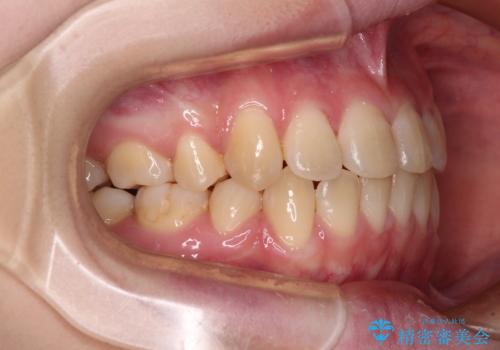

- 上下前歯が前方に飛び出しているとのことで来院された患者様です。

上下左右第一小臼歯4本を抜歯して、積極的に口元を引っ込めるよう、ワイヤー装置にて矯正治療を行うこととしました。

口元の突出感は著しく改善され、横顔の印象が大きく変化しました。